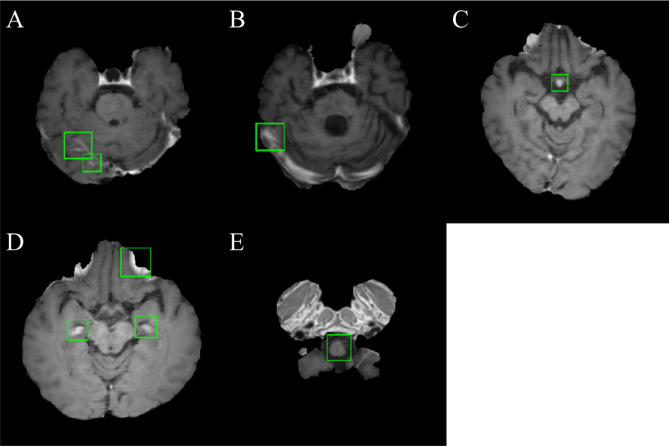

An example of a patient with five metastatic lesions of non-small cell lung carcinoma is shown in Fig. 1. Table 1 shows the performance of the five-fold cross-validation of DLA. The overall performance was 87.95%, 24.82%, 19.35%, 14.48, and 18.40 for the sensitivity, precision, F1-Score, and false positive average (FPavg) for the training cohort and normal individual dataset, respectively. For five-fold cross validation, the maximum and minimum sensitivities were 97.44% (DataSet5) and 81.82% (DataSet3), respectively, and the maximum and minimum FPavg were 21.57 (Model 2) and 7.27 (Model 3), respectively. Figure 2 shows examples of false positives from the DLA. The regions where false positives were mainly found were insufficiently suppressed in the vessel region. In addition, false positives were often observed in the choroid plexus, medulla oblongata, and basilar artery.

Figure 2.

Examples of a typical false positive from the DLA. Sample of sampling perfection with application-optimized contrasts using different flip-angle evolution (SPACE) images demonstrated false positive regions around insufficiently suppressed vessel (A, B), basilar artery (C), choroid plexus (D), and medulla oblongata (E). False positives were overlaid with green boundary boxes. This figure was generated by MATLAB (MathWorks, R2020b, Natick, MA, USA).